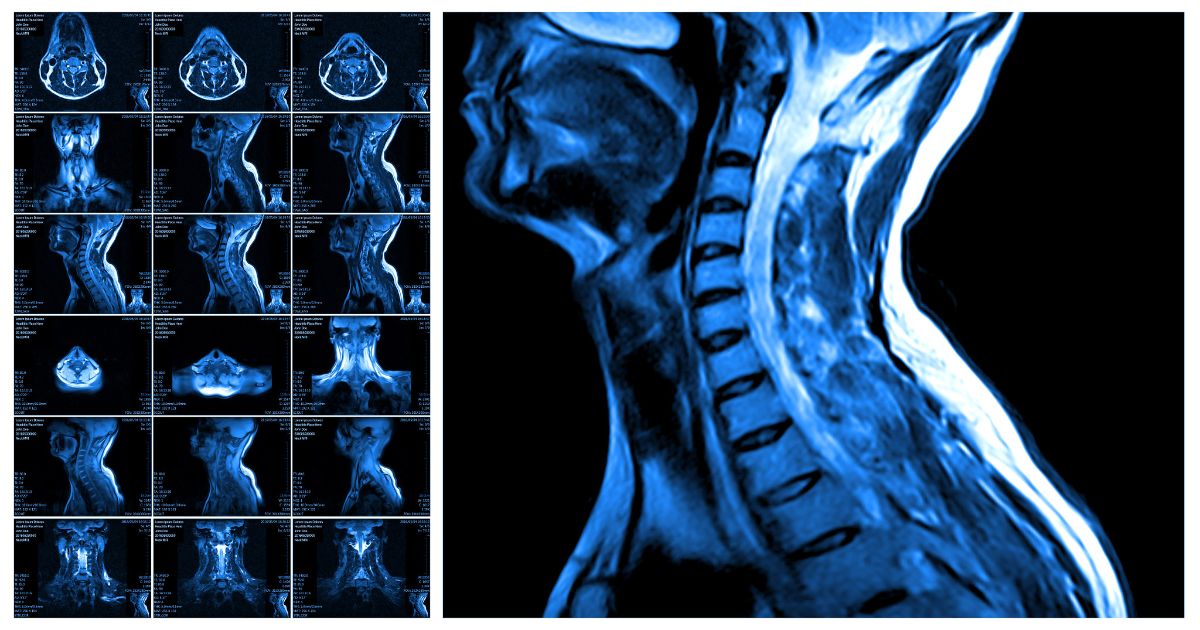

Basics of MRI for Physios Part 1 Radiology Nitin K Arora, Physiotherapy Researcher. Let's walk through an example -- The patient is a 52 year old man. According to APTA only 7 states and the District of Columbia expressly permit physical therapists to order imaging (MRI, xray, CT, etc)